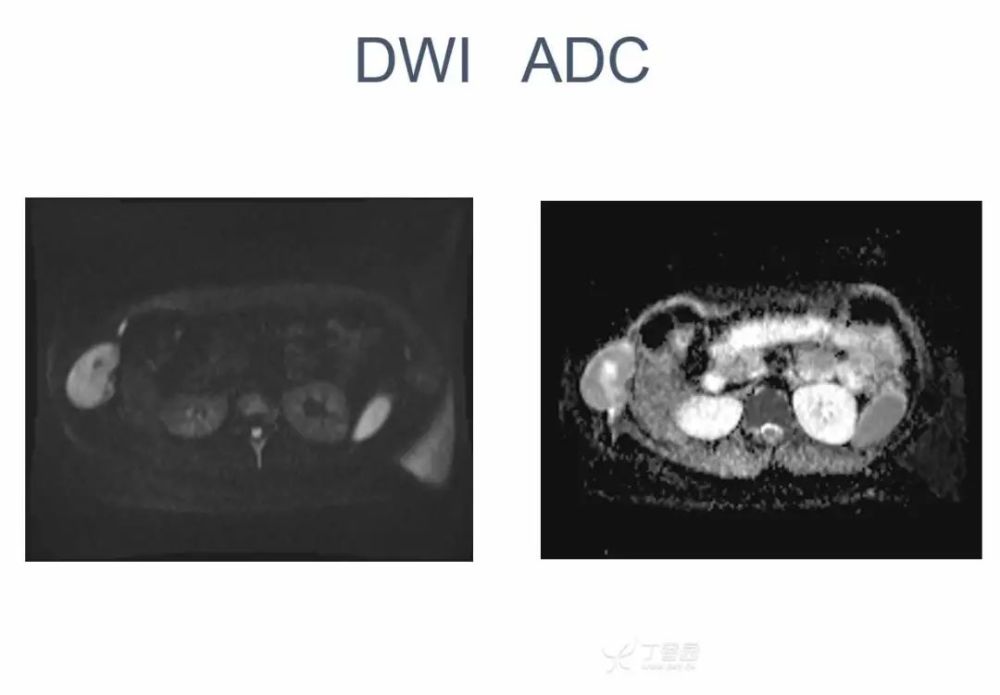

女,22 岁。右下侧胸壁疼痛、不适 10 年,近 3 年发现右侧腋中线近肋弓处肿块。体检:局部皮肤无红肿,肿块质中等偏硬,活动度欠佳,压痛( + ),无血管杂音。超声描述「低回声包块」。化验室指标无异常。